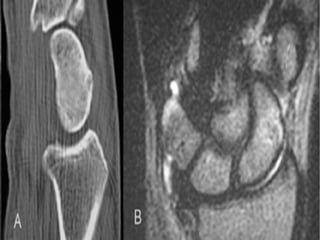

CT Scans

 CT permits accurate anatomic assessment of the fracture.

 Bone contusions are not evaluated with CT, but true fractures

can be excluded

MRI

• T1-weighted images obtained in a single plane (coronal) are

typically sufficient to determine the presence of a scaphoid

fracture.

• Gaebler prospectively performed MRI on 32 patients, at

average of 2.8 days post injury

– 100% sensitivity and specificity

• In recent study Dorsay has shown that immediate MRI

provides cost benefit when compared to splintage and repeat

xray

• False positives due MRI’s sensitivity to marrow oedema

CT Scans  CTpermits accurate anatomic assessment of the fracture.  Bone contusions are not evaluated with CT, but true fractures can be excluded

MRI • T1-weighted imagesobtained in a single plane (coronal) are typically sufficient to determine the presence of a scaphoid fracture. • Gaebler prospectively performed MRI on 32 patients, at average of 2.8 days post injury – 100% sensitivity and specificity • In recent study Dorsay has shown that immediate MRI provides cost benefit when compared to splintage and repeat xray • False positives due MRI’s sensitivity to marrow oedema